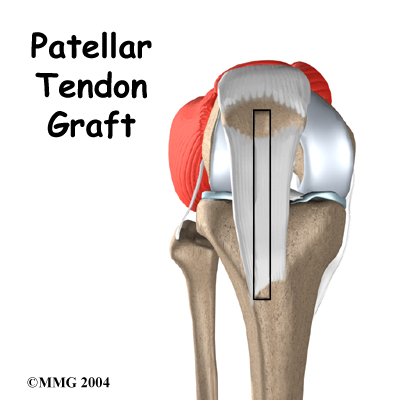

Patellar Tendon Graft Reconstruction of the ACL

The anterior cruciate ligament (ACL) is a major stabilizer of the knee joint. This key knee ligament is commonly torn during sports activities. The standard operation to fix a torn ACL is with a patellar tendon graft. The surgeon takes out the middle section of the patellar tendon below the kneecap (patella). This new graft includes the strip of tendon, along with attached plugs of bone on each end. For this reason, it is sometimes referred to as a bone-patellar-tendon-bone graft. The surge...